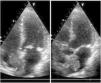

Mixoma biauricular gigante a través de comunicación interauricular

Large biatrial myxoma through an atrial septal defect